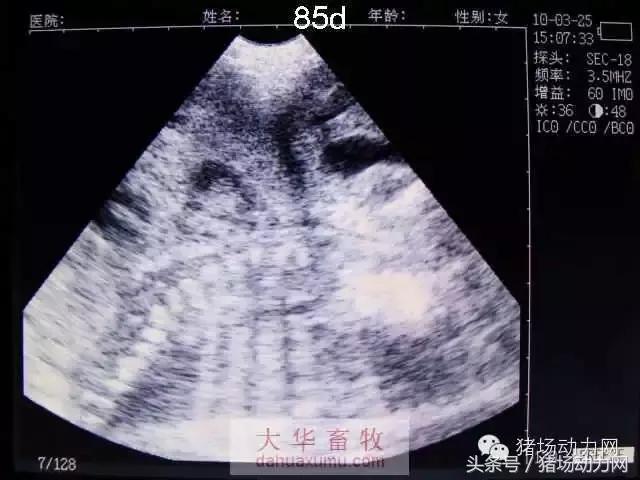

以下为怀孕母猪21天到90天之内的变化图:

85天